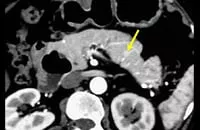

EUS画像(インスリノーマ例)

局在診断に関しては、CTや内視鏡的超音波断層検査(EUS)で腫瘍が分かる場合もありますが、腫瘍が描出されない時には、カルシウムを用いる選択的動脈内刺激薬注入試験(SASI Test)を行います。